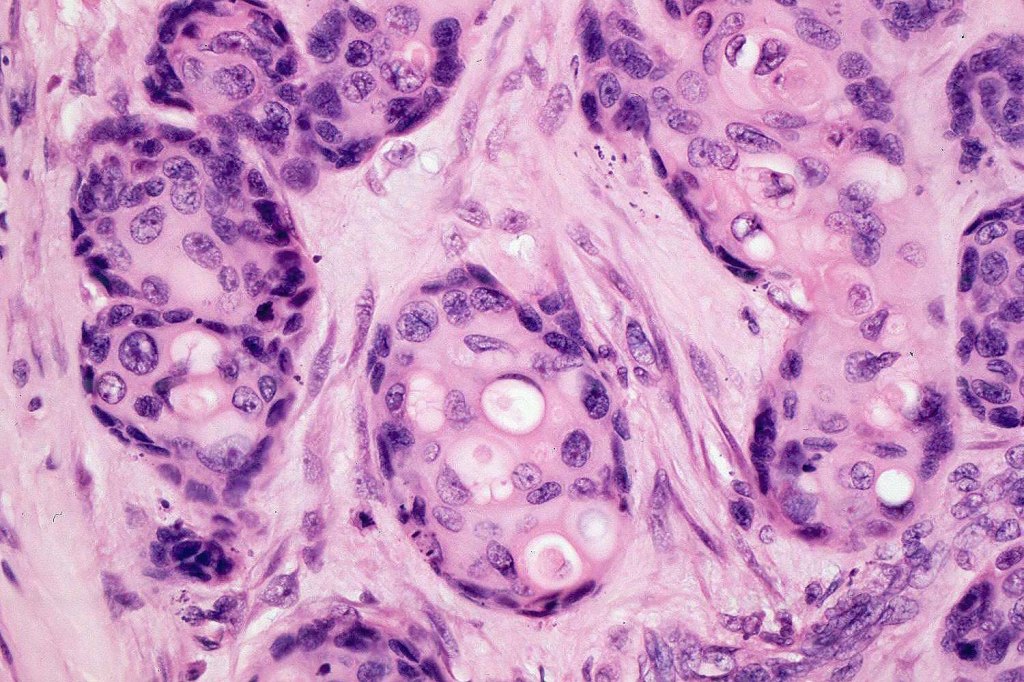

Histological features

•Ducal differentiation invariably present

•Intracytoplasmic lumina

•Squamous differentiation

•Broad anastomosing epithelial trabeculae